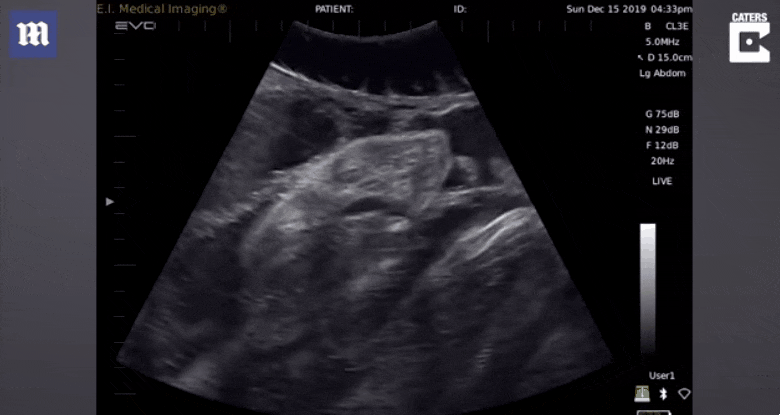

연구진은 보트 곁에 묶인 암컷 뱀상어의 배를 초음파 기기로 관찰하는 동시에, 어미 상어의 뱃속에서 자라는 태아 상어가 내는 소리를 동시 녹음했다.

그 결과 길쭉한 머리와 코, 큰 입 등이 선명한 태아 상어의 외형을 확인할 수 있었다. 뿐만 아니라 어미 뱃속에서 활발하게 활동하는 태아의 모습도 고스란히 촬영됐다.

대부분의 임신한 어미 뱀상어의 뱃속에서는 여러 마리의 새끼 상어가 자라고 있었으며, 이들은 어미 뱃속에서 한데 엉켜 움직이며 세상 밖으로 나갈 날을 기다리고 있었다.

연구를 이끈 제임스 술리코우스키 박사는 “초음파 영상을 통해 아직 엄마 뱃속에 있는 아기 상어를 보는 일은 절대 잊을 수 없는 놀라운 경험이었다”면서 “우리는 이 지역에 서식하는 뱀상어의 움직임을 면밀하게 관찰했으며, 이는 개체 수를 보존하는데 도움이 될 것”이라고 설명했다.